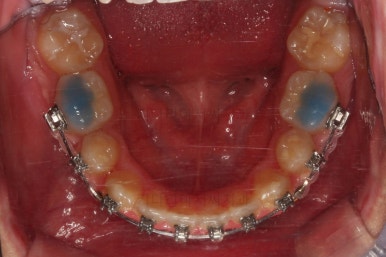

입이 많이 안들어가야 하는 케이스라 얼굴모습을 중간중간 확인을 많이 해주고요.

남은 공간을 자연ㅇ스럽게 더 닫아주고요.

마무리 하게 됩니다.

총 19개월만에 치료를 종료했습니다.

가지런한 느낌, 교합, 중앙선 등 매우 양호한 치료결과였습니다.